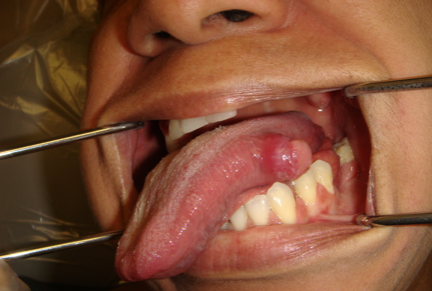

- A sore or ulcer that fails to heal and bleeds easily.

- A lump or thickening on the skin lining the inside of the mouth.

- Skin Lesions